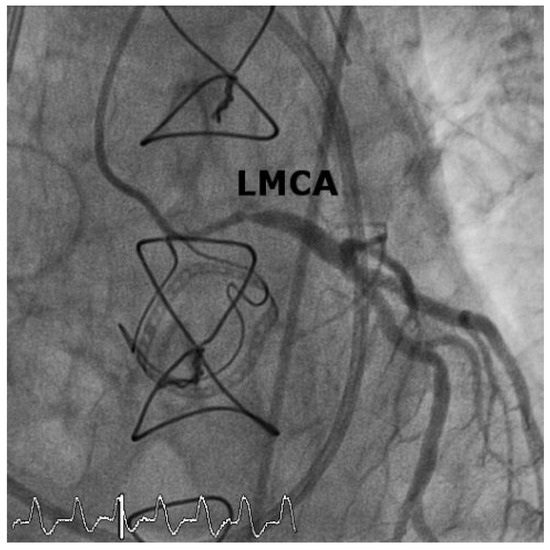

Case2